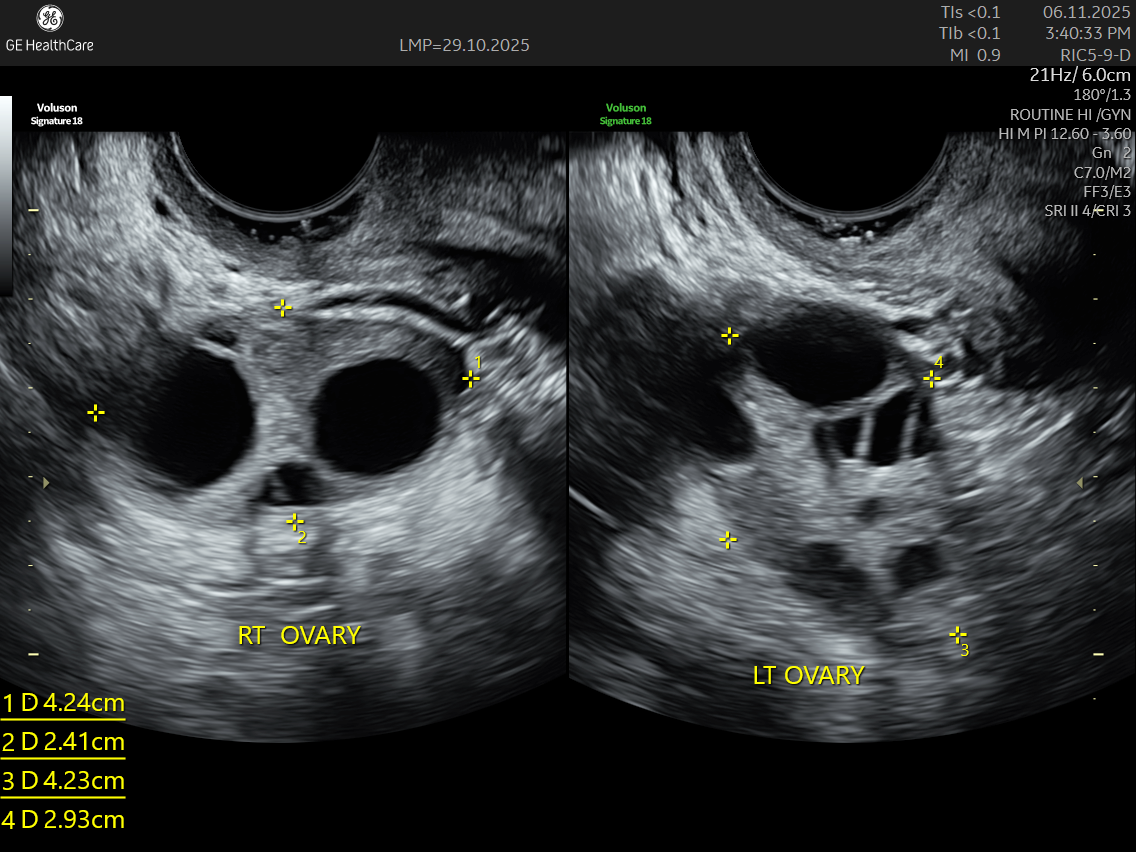

IMAGE GALLERY